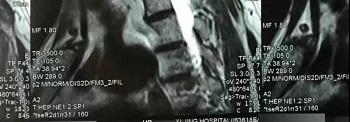

十二、拍摄时,尽可能的将片子上的文字信息拍摄清楚,并将左右拍摄清楚(片子上有标R,表示右侧right,L, 表示左侧left的意思), 每张片子上的文字都能按照阅读习惯拍正确,不要拍反了。

拍摄时,必须要对着片子上的文字对焦, 方向正确,将文字拍摄得清晰可视,保证放大图片后文字依然清晰可见(如下图),尽可能多的保留片子上的信息。